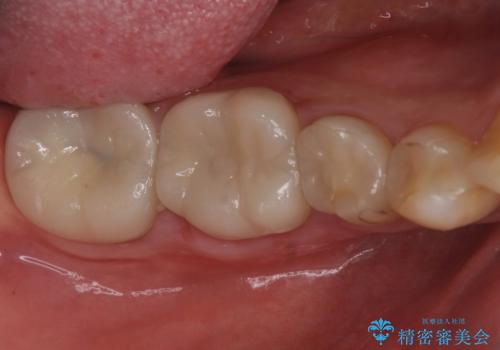

樹脂で継ぎ接ぎになった歯 セラミッククラウンでの治療

- 樹脂の材料の着色が気になるとのことで来院されました。

継ぎ接ぎになっている部分が多かったためクラウンでの治療となりました。

樹脂の材料と歯の境界部分は虫歯・着色の好発部位となります。

度重なる治療で継ぎ接ぎになってしまった場合はクラウンで歯を覆った方が虫歯・着色のリスクを減らすことができます。